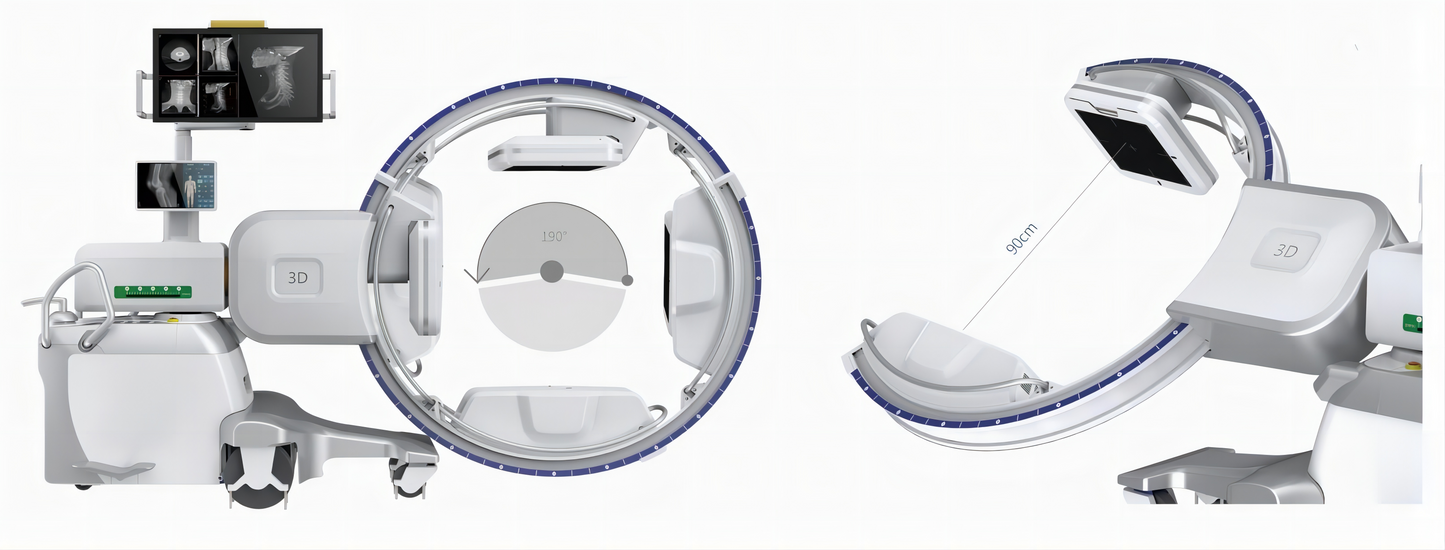

GHM-750 Digital Intraoperative 3D C-arm System

GHM-750 is equipped with a 30cm× 30cm dynamic flatpanel. As an "intraoperative CT", it can quickly generate CT-like tomographic images and stereoscopic 3D images during surgery, providing more comprehensive image information for the surgeons and precise observation of the implant, such as the position and angle of the screw for internal screw fixation. GHM-750 is a model with clear imaging, easy operation and convenient positioning, mainly used in operating rooms for orthopedics, spine surgery, trauma orthopedics, etc. It can significantly improve the surgical results and reduce the probability of surgical risks and complications.

5. Isocentric Rack Design

GHM-750 adopts isocentric design, providing a larger opening space (90cm) suitable for the requirements of various clinical positions. The design avoids the movement of the C-arm frame in the horizontal and vertical directions during 3D image acquisition, and always keeps the exposed part in the X-ray’s center, which reduces motion artifacts andimproves image clarity.